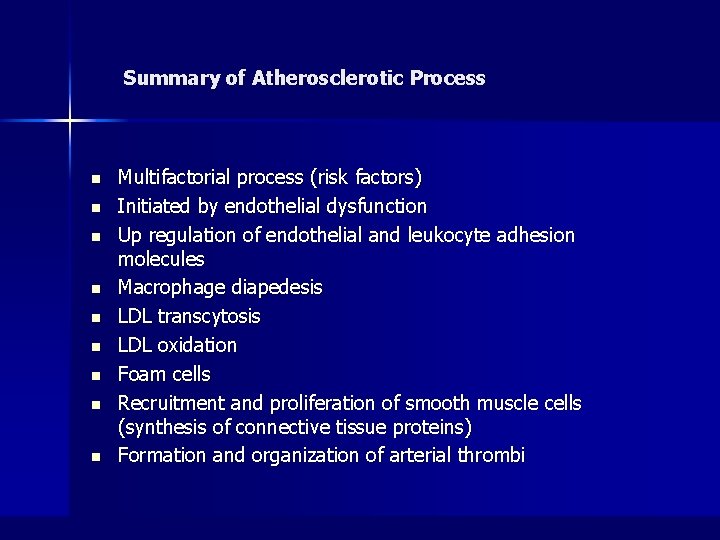

Summary of Atherosclerotic Process n n n n n Multifactorial process (risk factors) Initiated by endothelial dysfunction Up regulation of endothelial and leukocyte adhesion molecules Macrophage diapedesis LDL transcytosis LDL oxidation Foam cells Recruitment and proliferation of smooth muscle cells (synthesis of connective tissue proteins) Formation and organization of arterial thrombi